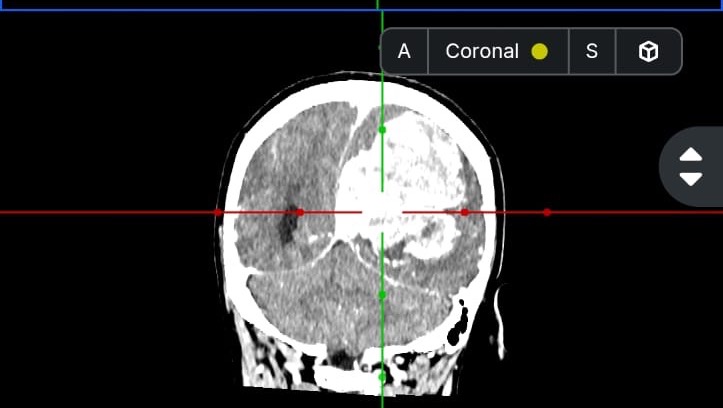

Hola me llamo Lucia del Carmen Morales Auvert tengo 38 años y estoy recaudando fondos ya que tengo que ser intervenida de emergencia debido a un proceso expansivo intracerebral y no cuento con los recursos necesarios para cubrir dicha operación, a su vez tengo que realizarme una Angiografia, gastos médicos y gastos quirúrgicos.

En este momento me van a realizar una embolizacion. Es un procedimiento para tratar vasos sanguíneos anormales en el cerebro y otras partes del cuerpo. Este procedimiento interrumpe el riego sanguíneo a cierta parte del cuerpo. Para después realizar la cirugía